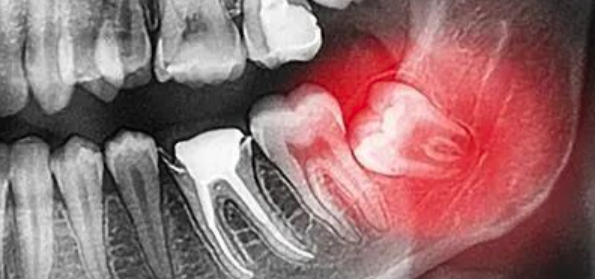

药物相关性颌骨坏死(MRONJ)是一种因治疗全身其他疾病需使用骨吸收抑制剂、抗血管生成类药物、类固醇类药物/激素类药物等后而引起的颌骨代谢紊乱、严重颌骨坏死并发症,可出现于上下颌骨,下颌骨的比率是上颌骨的3倍,也可出现在双颌。MRONJ为正使用或曾使用过骨吸收抑制剂,及单用或合用过抗血管生成药物、免疫抑制剂,无颌骨转移性肿瘤疾病、颌骨放射治疗史,但颌面部有死骨暴露,或通过口内/外瘘探及骨面持续>8周。

表现为局部红肿、流脓、疼痛、溃疡或剥脱、咀嚼障碍、开口受限、骨外露、瘘管形成、口外或口内窦道、麻木、面部软组织瘘管经久不愈、颌骨坏死、病变区牙松动脱落、死骨暴露、间隙感染、伤口长期不愈等,严重时可伴病理性骨折,严重影响饮食等功能、生活质量及身心健康,可分期为4期即0期、I期、II期、III期。